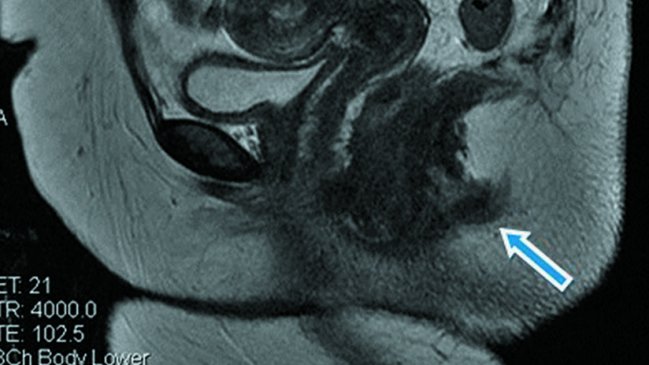

La paciente, cuya identidad no fue revelada, primero acudió a un chequeo médico pues tenía abscesos en la zona. Al pasar por las máquinas de resonancia, los especialistas confirmaron que tiene una “estructura tubular posterior al canal anal”.

Su segundo orificio fue descrito por los médicos como una cavidad de solo tres centímetros de profundidad y un centímetro de ancho que no está conectada a las paredes rectales.